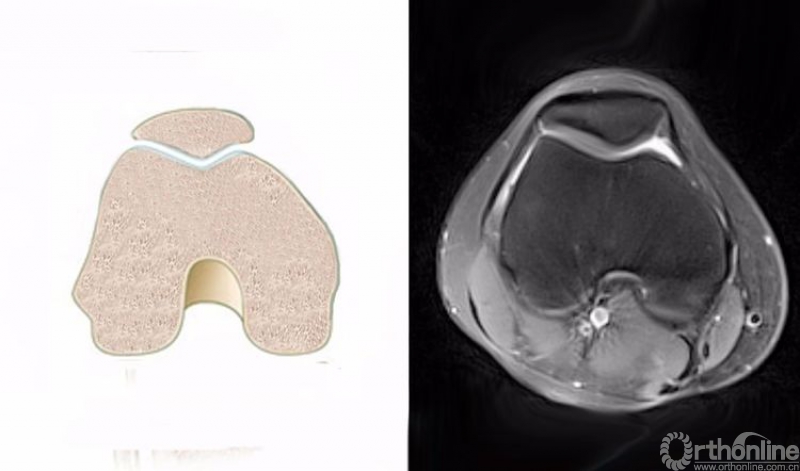

正常的膝关节进行MRI扫描时,不管任何一个序列,其骨髓信号一般T1WI呈均匀一致的灰色,T2WI及STIR呈均匀一致的黑色。

3.膝关节轴位的正常MRI图像